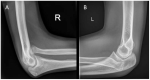

Osseous deformities in children arise due to progressive angular growth or complete physeal arrest. Clinical and radiological alignment measurements help to provide an impression of the deformity, which can be corrected using guided growth techniques. However, little is known about timing and techniques for the upper extremity. Treatment options for deformity correction include monitoring of the deformity, (hemi-)epiphysiodesis, physeal bar resection, and correction osteotomy. Treatment is dependent on the extent and location of the deformity, physeal involvement, presence of a physeal bar, patient age, and predicted length inequality at skeletal maturity. An accurate estimation of the projected limb or bone length inequality is crucial for optimal timing of the intervention. The Paley multiplier method remains the most accurate and simple method for calculating limb growth. While the multiplier method is accurate for calculating growth prior to the growth spurt, measuring peak height velocity (PHV) is superior to chronological age after the onset of the growth spurt. PHV is closely related to skeletal age in children. The Sauvegrain method of skeletal age assessment using elbow radiographs is possibly a simpler and more reliable method than the method by Greulich and Pyle using hand radiographs. PHV-derived multipliers need to be developed for the Sauvegrain method for a more accurate calculation of limb growth during the growth spurt. This paper provides a review of the current literature on the clinical and radiological evaluation of normal upper extremity alignment and aims to provide state-of-the-art directions on deformity evaluation, treatment options, and optimal timing of these options during growth.